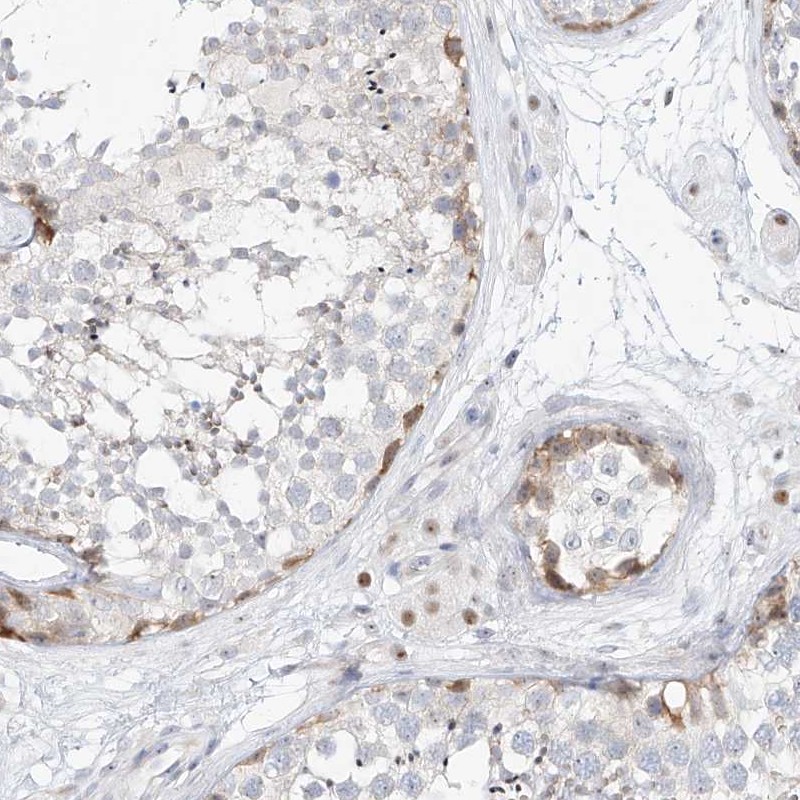

Immunohistochemical staining of human testis shows moderate nuclear positivity in Leydig and seminiferous ducts cells.